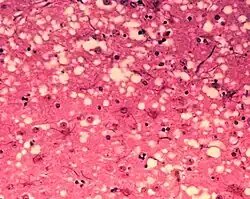

Für die Erkrankung sind Prion-Proteine charakteristisch. Das sind abnorme Proteine (PrPSc), die im befallenen Gehirn durch Umfaltung aus der normalen Form des Proteins (PrPC) hervorgehen. So wird ein biochemischer Prozess ausgelöst, der zur Ablagerung des umgefalteten Proteins und in der Folge zur Degeneration des Hirngewebes führt. Bei fortschreitender Erkrankung nimmt das befallene Gehirn eine schwammartig durchlöcherte Struktur mit fadenförmigen, proteinhaltigen Ablagerungen an.

Bei der Krankheit wird das Gehirn schwammartig durchlöchert und damit in seinen Funktionen gestört. In Gewebeproben lassen sich die oben genannten Prionen nachweisen.

- Histologie: Nachweis der Vakuolen (Hohlräume)